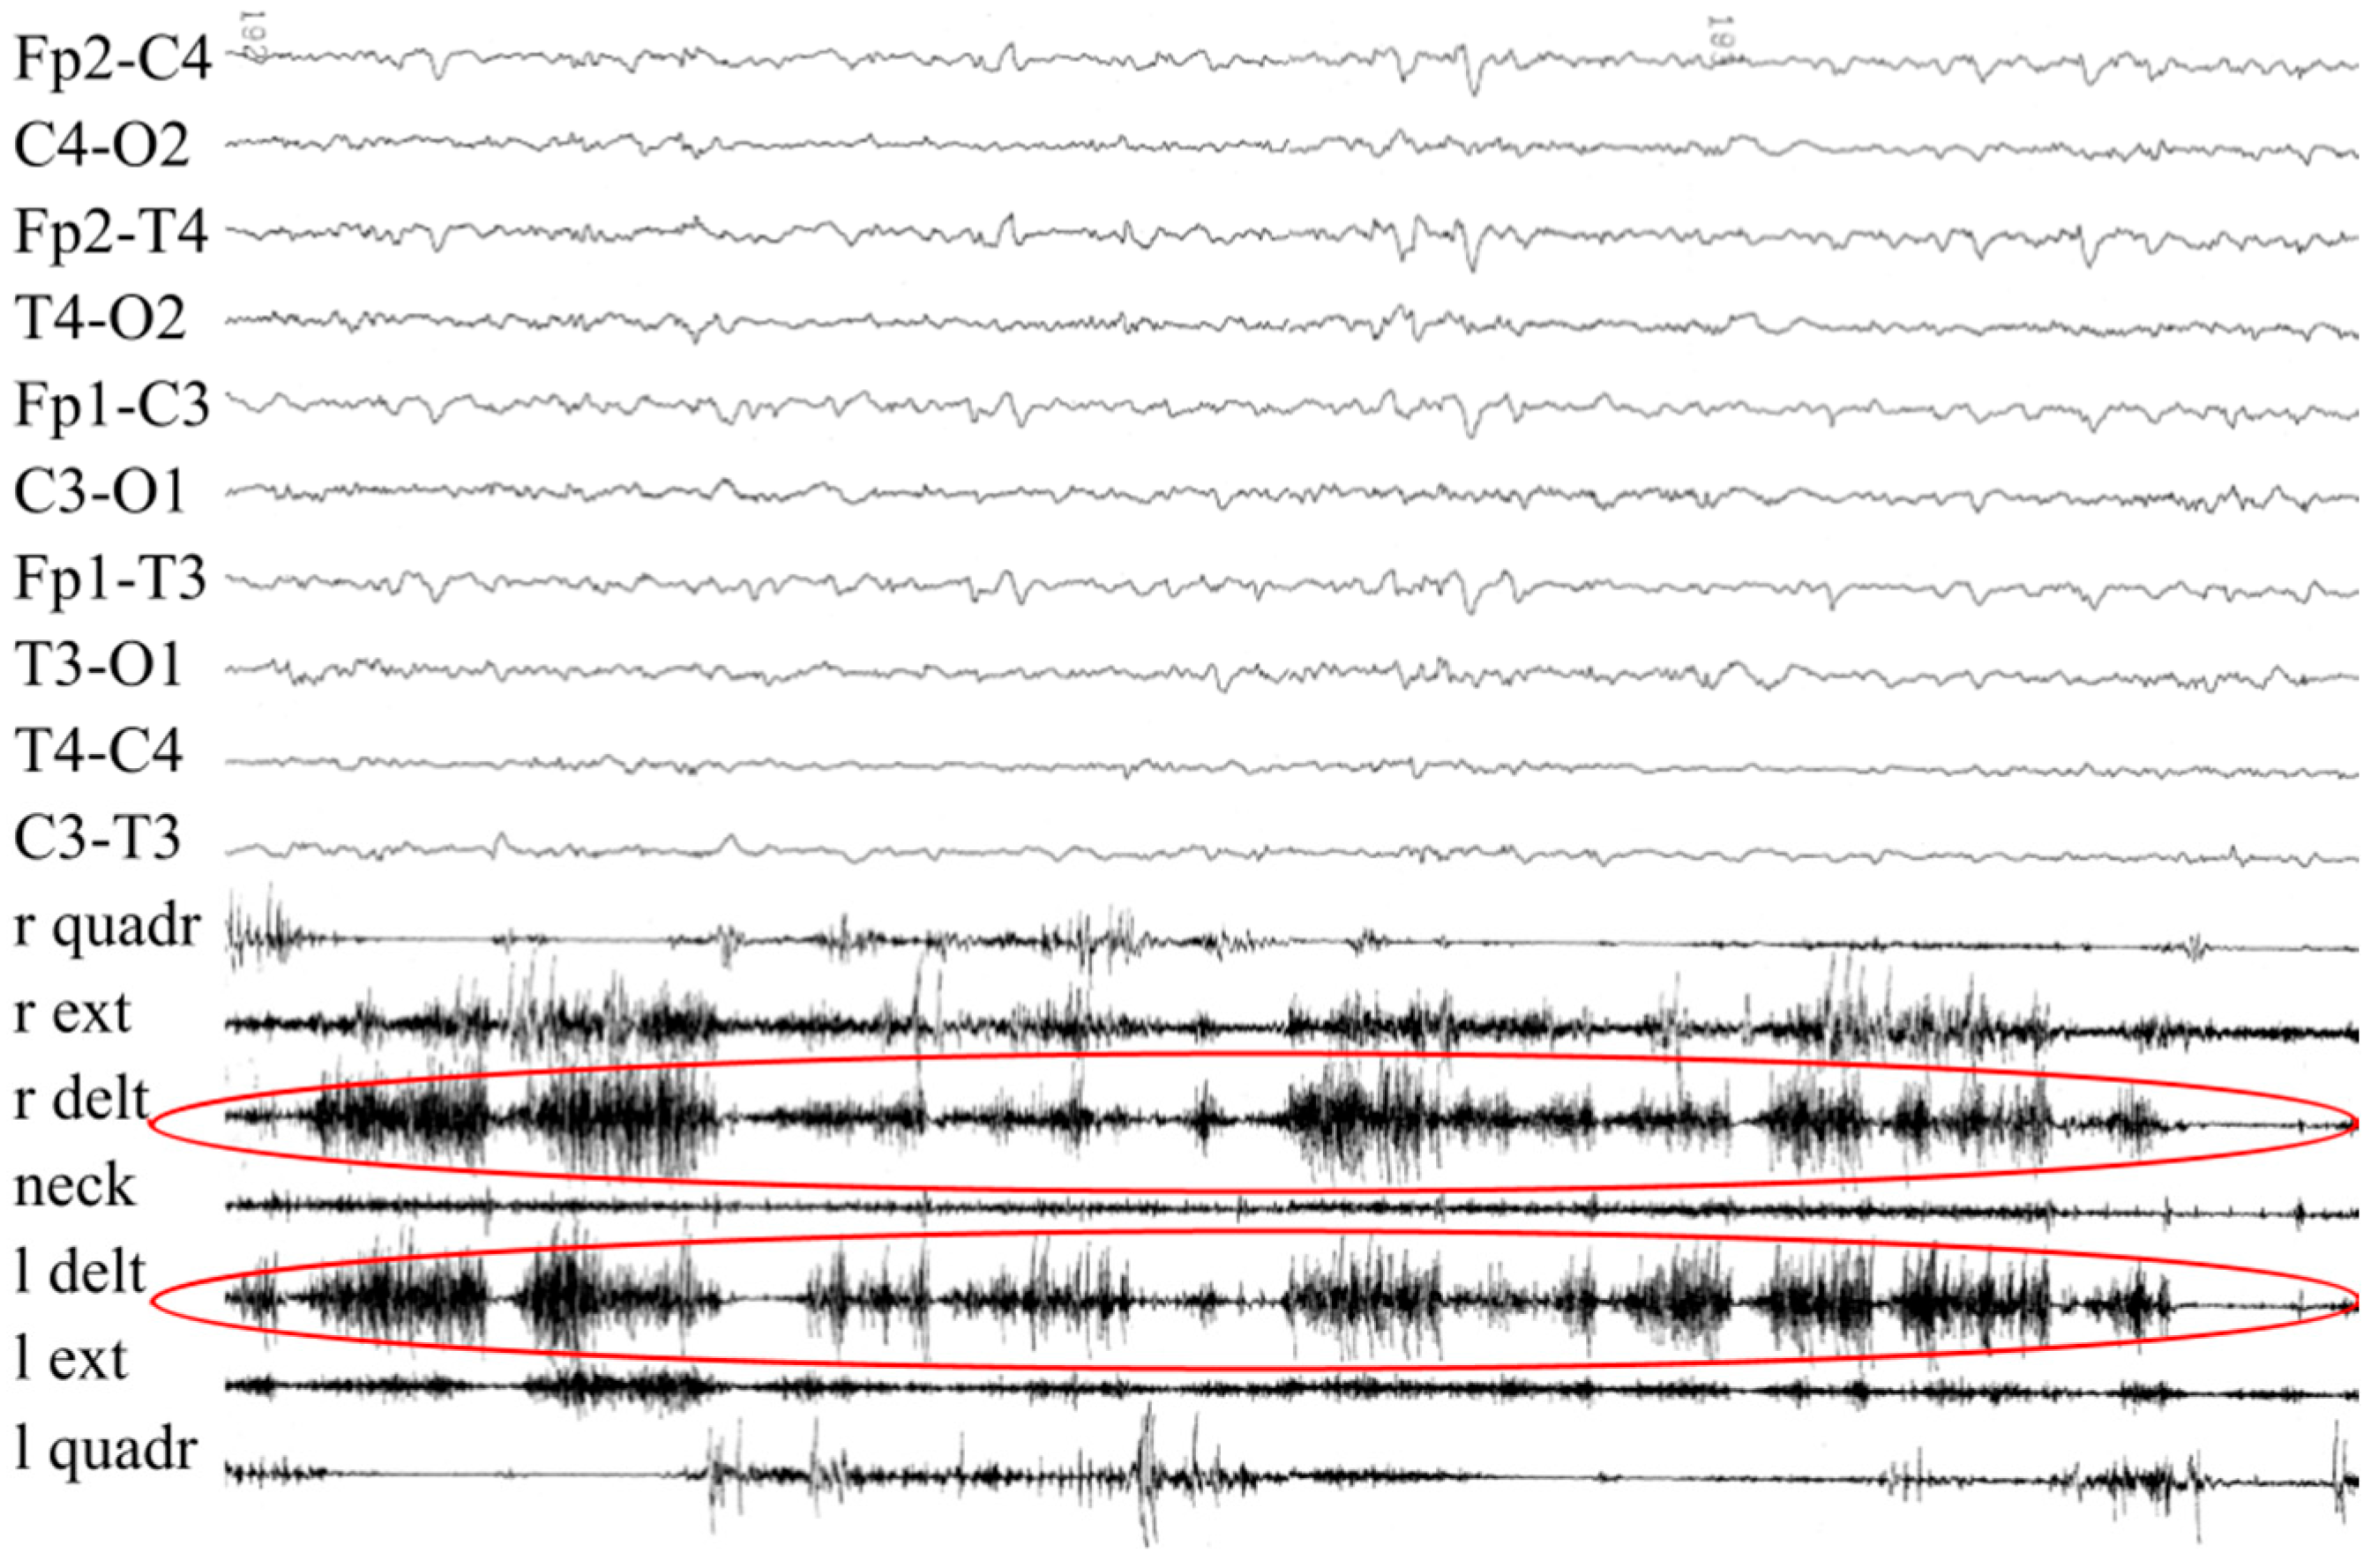

3.1. Patient #1

| Evidence prompting suspicion of cs/ciss | Orofacial muscle contractions, generalized paroxysmal events, camptodactyly | Prenatal bilateral camptodactyly |